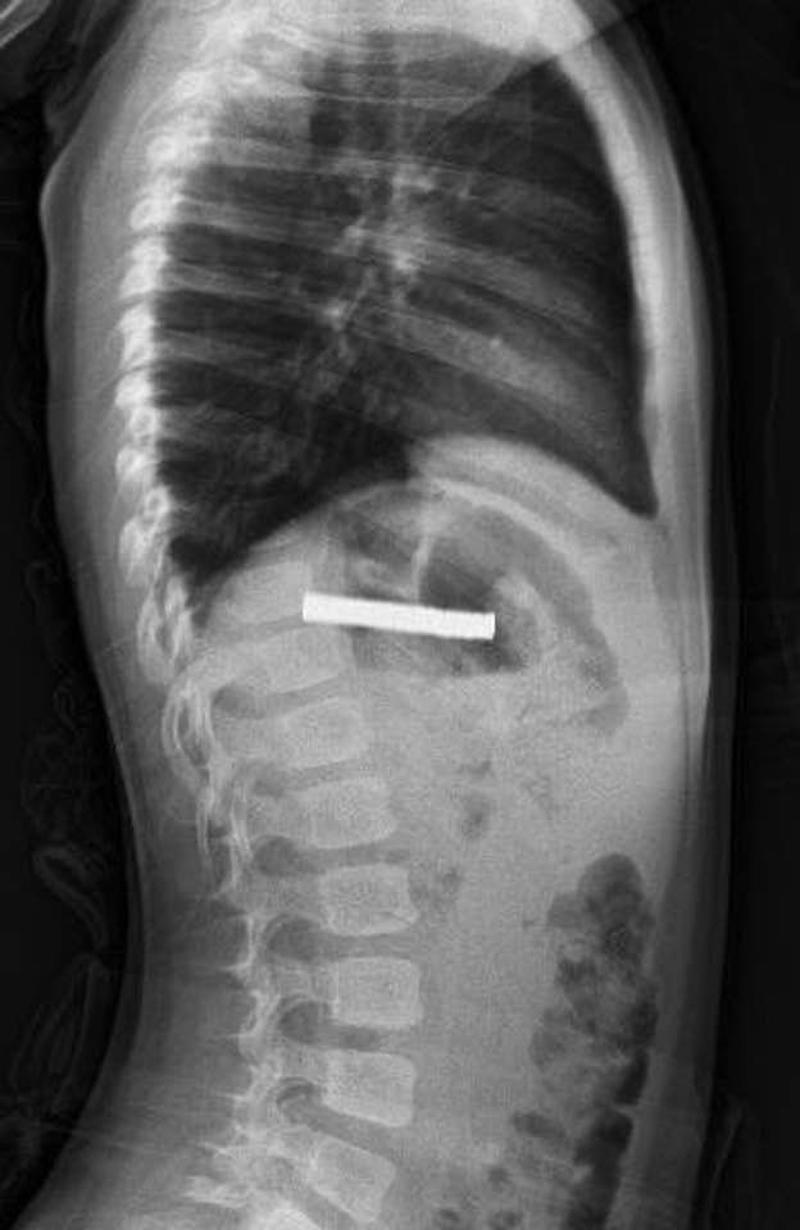

Edinilen bilgiye göre, Erzurum'da bir çocuk evde bulunan 19 tane mıknatısı yuttu. Çocuğun rahatsızlanması sonucu durumu öğrenen aile hastaneye başvurdu. Daha sonra çocuk Elazığ'a sevk edildi.

3 YAŞINDAKİ ÇOCUĞUN BOĞAZINDAN 19 TANE MIKNATIS ÇIKARTILDIFırat Üniversitesi Çocuk Gastroenteroloji Hepatoloji ve Beslenme Bilim Dalı Başkanı Prof. Dr. Yaşar Doğan, çocuk hastanın yemek borusuna yapışmış 19 mıknatısı endoskopik yöntemle çıkardı.

Mıknatıslar uzun süre yemek borusunda takılı kaldığı için yemek borusu ve mide girişinde zedelenmeler olurken, çocuğun sağlık durumunun iyi olduğu ve taburcu edildiği öğrenildi.